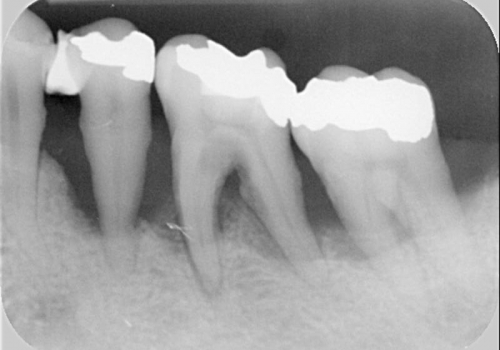

Çünki bu ciblər çox zaman pasiyent tərəfindən yetərincə təmizlənə bilmir. Bu isə həmin bölgəyə tədricən ərp və dolayısı ilə də bakteriya koloniyalarının toplanmasına səbəb olur. Bu proses yenidən yerli iltihabın ortaya çıxmasına səbəb olur. Tətbiq edilən cərrahi metodlar əsasən cibin yerləşdiyi diş bölgəsi, cibin eni, dərinliyi, konfiqurasiyası və s. xüsusiyyətlərə görə müəyyənləşdirilir. Bu zaman məqsəd mümkün olduqda həmin bölgədə bərpa prosedurunu həyata keçirmək, mümkün olmadıqda isə rezektiv müalicənin tətbiqi ilə həmin bölgəyə ərp toplanma ehtimalını azaltmaq və gigiyenik prosedurların icrasını pasiyent üçün rahatlaşdırmaqdır.

Rezektiv prosedurlar zamanı müəyyən miqdarda yumuşaq toxuma (diş əti), sərt toxuma (sümük) və ya kombinə olunmuş şəkildə (həm sümük, həm də yumuşaq toxuma) rezeksiya həyata keçirilir. Prosedur yerli ağrısızlaşdırma altında aparılır. Əməliyyatdan sonrakı dövrdə fərdi qulluq və gigiyena qaydalarının mötəxəssis tərəfindən izahı və müvafiq instruksiyanın verilməsi olduqca önəmlidir.